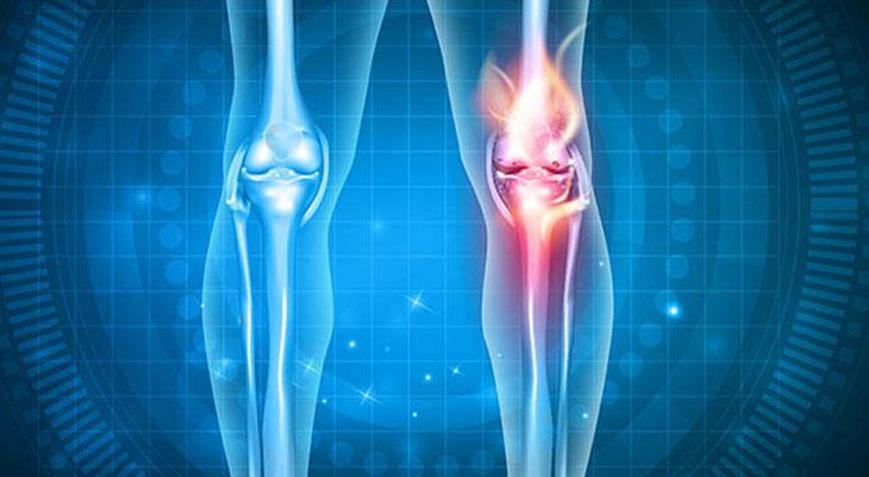

Osteoporoz yani kemik erimesi, kemik kütlesinde azalma ile karakterize genel bir iskelet hastalığıdır. Bizler de sizin için kemik erimesine ne iyi gelir, nasıl geçer? Erimeyi önleyen şeyler nelerdir? Tedavi yöntemleri nelerdir tüm detayları derledik.

Kemik kütlesindeki azalma, kemik mikro yapısındaki bir değişiklik ile ilişkilidir, bu da kemik kırılganlığında bir artışa ve artan bir kırılma riskine yol açar.

Kemik Erimesi Nedir?

Yaşla birlikte protein yapısındaki azalma normal bir fenomendir, iskeletin yaşlanmasına bağlı fizyolojik osteopenidir. Osteoporoz bu fenomenin bir kaçağıdır. Kemik, sürekli yenilenen dinamik bir organdır. Eski kemik periyodik olarak yok edilir ve aynı bölgede yeni kemik materyali yapılırken elimine edilir.

Kemik yeniden şekillenmesi normal bir şekilde gerçekleşmezse (yetersiz kemik oluşumu), kendini kortikal kemikten daha hızlı yenilemesi gereken süngerimsi kemik, en hızlı şekilde osteoporoz riski altında olacaktır.

Kemik yıkımı ve oluşum aktiviteleri, kemik matriksinde veya hormonlarda bulunan birçok yerel faktör tarafından hassas düzenleme sayesinde normal olarak dengelenir. Dengeleme olmazsa kemik erimesi oluşur.